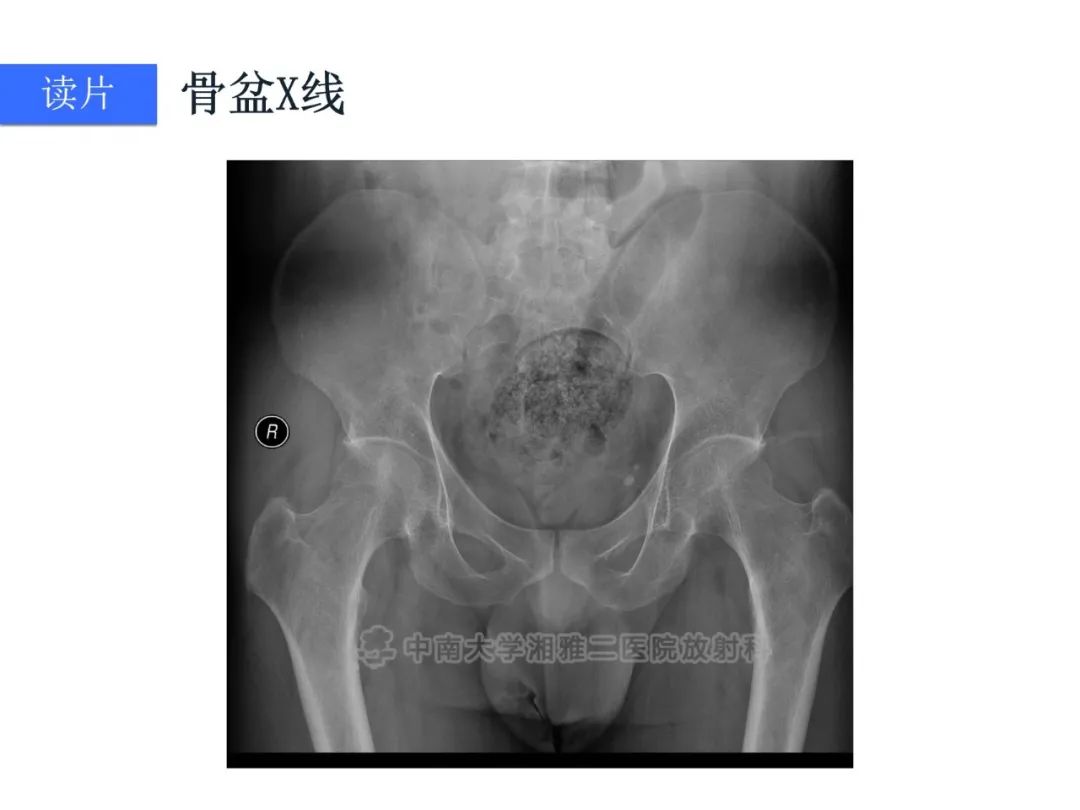

【病例】磷酸盐尿性间叶性肿瘤1例影像学诊断思路-1